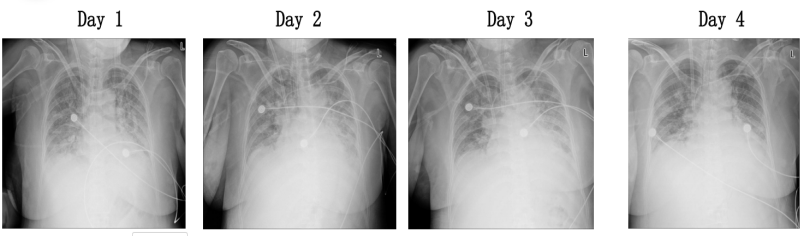

影像学检查显示,患者肺部病变逐渐吸收,出院前复查肺部CT提示肺部浸润影基本消退(图6)。患者住院期间度过除夕及元宵,经过规范治疗后顺利出院,出院后复查肺部情况持续好转(图7),多器官功能恢复正常。

图片

6  患者治疗期间胸片变化情况